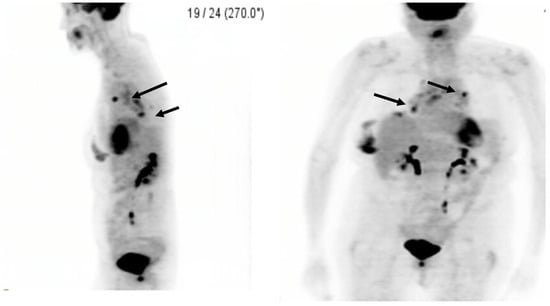

2. Case Presentation